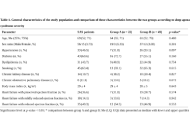

DOI: https://doi.org/10.37349/emed.2025.1001311 Long-term neurological and otolaryngological sequelae of COVID-19: a retrospective studyOpen AccessOriginal ArticleAim: COVID-19, a multisystemic syndrome caused by SARS-CoV-2, often results in long-term complications collectively referred to as long COVID. This study explores the persistence of neurological [...] Read more.Wael Abu Ruqa ... Antonio MinniPublished: April 21, 2025 Explor Med. 2025;6:1001310

Long-term neurological and otolaryngological sequelae of COVID-19: a retrospective studyOpen AccessOriginal ArticleAim: COVID-19, a multisystemic syndrome caused by SARS-CoV-2, often results in long-term complications collectively referred to as long COVID. This study explores the persistence of neurological [...] Read more.Wael Abu Ruqa ... Antonio MinniPublished: April 21, 2025 Explor Med. 2025;6:1001310